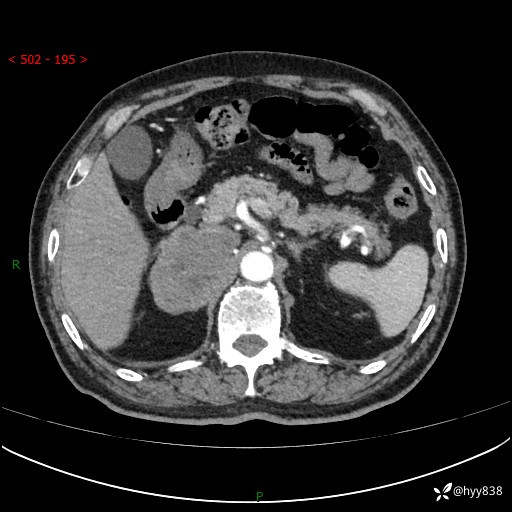

【患者信息】:76岁/男

【主诉】:检查发现右侧肾上腺占位6天

【现病史及既往史】:患者6天前体检发现右侧肾上腺占位,无腰痛,无放射痛,无尿频、尿急、尿痛及肉眼血尿,无畏寒、发热,无恶心、呕吐,今为求进一步治疗,遂来我院就诊,门诊拟“右侧肾上腺占位”收住入院。 起病以来,患者精神、饮食、睡眠可,大小便如常,体力体重无明显变化。

【检查】:肾上腺CT平扫+增强